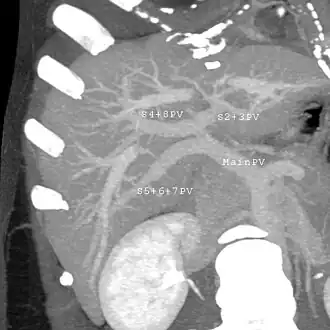

Couinaud classification system

Shape of human liver in animation, with eight Couinaud segments labelled

In the widely used Couinaud system, the functional lobes are further divided into a total of eight subsegments based on a transverse plane through the bifurcation of the main portal vein.[30] The caudate lobe is a separate structure that receives blood flow from both the right- and left-sided vascular branches.[31][32] The Couinaud classification divides the liver into eight functionally independent liver segments. Each segment has its own vascular inflow, outflow and biliary drainage. In the centre of each segment are branches of the portal vein, hepatic artery, and bile duct. In the periphery of each segment is vascular outflow through the hepatic veins.[33] The classification system uses the vascular supply in the liver to separate the functional units (numbered I to VIII) with unit 1, the caudate lobe, receiving its supply from both the right and the left branches of the portal vein. It contains one or more hepatic veins which drain directly into the inferior vena cava.[30] The remainder of the units (II to VIII) are numbered in a clockwise fashion:[33]

With the recent advances of noninvasive imaging, living liver donors usually have to undergo imaging examinations for liver anatomy to decide if the anatomy is feasible for donation. The evaluation is usually performed by multidetector row computed tomography (MDCT) and magnetic resonance imaging (MRI). MDCT is good in vascular anatomy and volumetry. MRI is used for biliary tree anatomy. Donors with very unusual vascular anatomy, which makes them unsuitable for donation, could be screened out to avoid unnecessary operations.